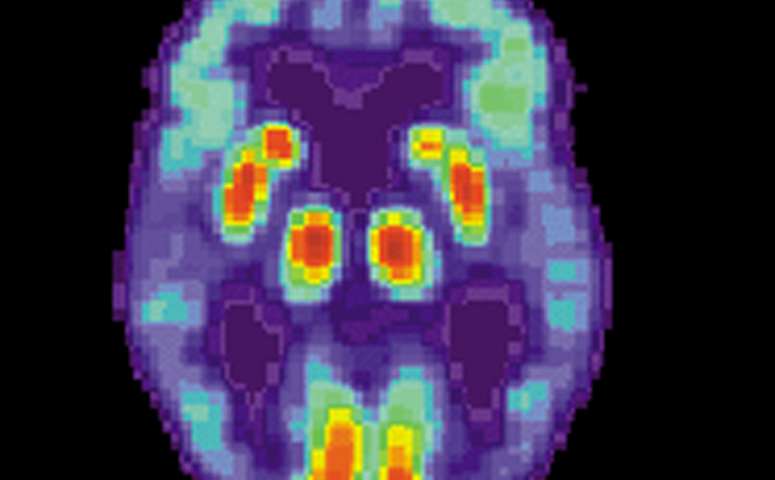

阿尔茨海默病患者的大脑PET扫描。

最新这项研究使用了巴尔的摩老龄化纵向研究(BLSA)的数据,这是一项由NIA在1958年开始的长期研究,跟踪了数千名志愿者的健康状况。作为定期检查的一部分,志愿者们在1991年至2000年期间填写了一份调查问卷。其中一组BLSA志愿者在1994年开始接受神经影像学评估。从2005年开始,一些参与者使用匹兹堡化合物B (PiB)接受正电子发射断层扫描(PET),这种放射性化合物可以帮助识别神经组织中的β-淀粉样蛋白。